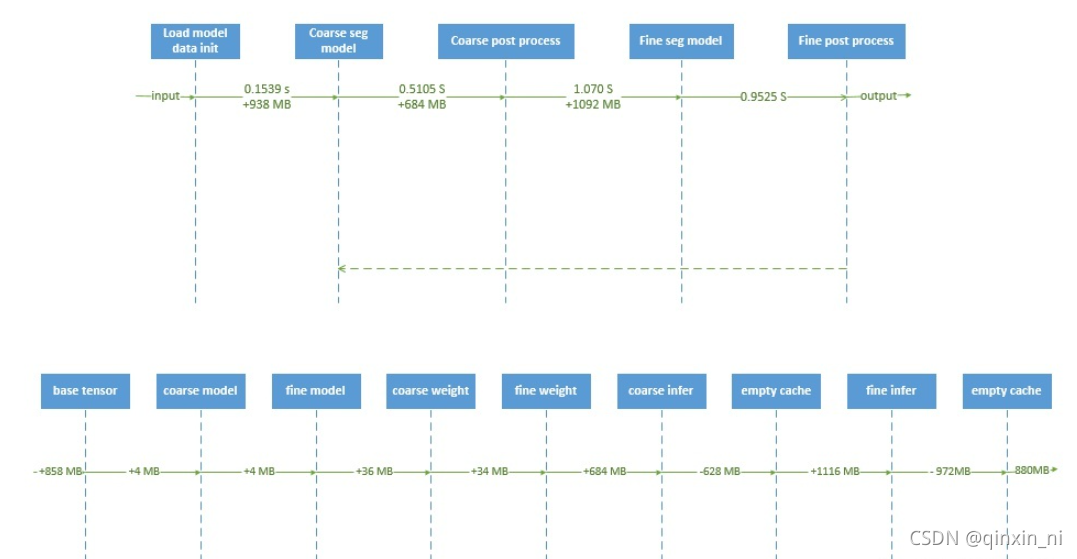

Network

EfficientSegNet网络,该网络由basic encoder、slim decoder和efficient context模块组成。在decoder模块中引入anisotropic卷积,提升了网络计算效率;设计mixed pyramid pooling的context模块,融入strip pooling结构,提升了anisotropic和long-range上下文特征的表示能力。相较于self-attention和non-local模块,strip pool具有更低的显存占用和矩阵运算量。算法实现上,采用混合精度、分布式训练技术来缩短训练过程时间,提升显存利用效率。在推理过程中,采用CUDA加速图像预处理和后处理,FP16量化推理提升模型推理效率。

Encoder/Decoder

如图所示,编码器模块由两个残差卷积块组成,解码器模块由一个残差卷积块组成。在解码器模块中,我们将一个核大小为3×3×3的标准3D卷积分离为3×3×1片内卷积和1×1×3片间卷积。残差卷积块的实现如下:convent -instnorm-ReLU- convent -instnorm-ReLU(残差的加入发生在最后一个ReLU激活之前)。

Context block

我们采用基于3D-based mixed pyramid pooling (3D的混合金字塔池化)方法提取背景特征,该方法由标准空间池化和各向异性条带池化两部分组成。标准空间池使用两个平均池,大小分别为2×2×2和4×4×4。anisotropic strip pooling具有三个不同方向的感受域:1×N×N, N×1×N, N×N×1,其中N为上一个编码器模块中feature map的大小。

粗模型初始特征图个数为8,细模型初始特征图个数为16。我们通过添加而不是连接来聚合低级的水平特性,因为前者消耗的GPU内存更少。此外,对于192×192×192输入大小,模型参数的数量是9 MB,失败的数量是333 GB。